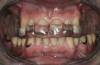

Initial examination revealed a partial edentulous patient with extensive wear of the maxillary anterior teeth and moderate wear in the mandibular teeth (Figure 1, Figure 2, Figure 3 , Figure 4, Figure 5, Figure 6 and Figure 7). The patient's maxillary and mandibular RPDs also showed excessive wear and multiple signs of fractures (Figure 2 and Figure 3). The patient had been wearing a mandibular nightguard for 8 years.

Figure 1  Intraoral anterior view of the patient presenting a severely worn maxillary dentition and loss of OVD.

Figure 1